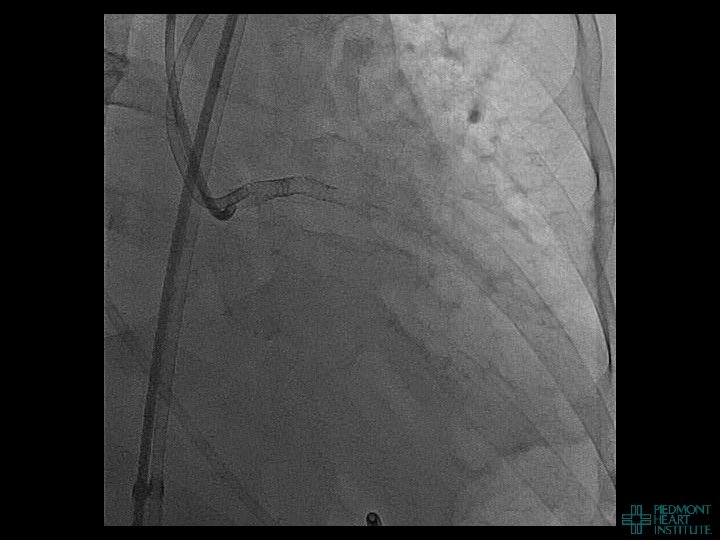

Coronary Perforation Methods of Patient Management • Dual Catheter (‘Ping Pong’) Technique • Prolonged

Coronary Perforation Methods of Patient Management • Dual Catheter (‘Ping Pong’) Technique • Prolonged balloon inflation and covered stents • Reversal of anticoagulation — Know contradictions to protamine sulfate for UFH; Avoid bivalirudin, LMWH — Reserve GP 2 b 3 a inhibition until successful crossing and wire change-out Embolization • — Coil, gelfoam, methacrylate, autologous blood/fat • Microcatheter Occlusion • Confirmation of successful management — Contralateral injection — Right heart catheterization — Echocardiogram — Contrast echocardiography